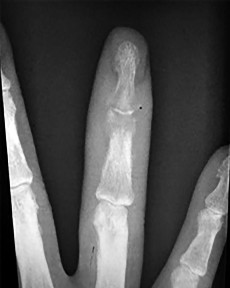

Figures 31a through 31d are the radiographs and MR images of a 52-year-old man who has a 7-week history of right ring finger pain, redness, and swelling. He accidentally stuck his finger with a toothpick 1 week before developing symptoms. There is purulent drainage from the puncture wound site. He was treated with oral antibiotics for 10 days and intravenous (IV) antibiotics for 3 weeks before being seen. Initial cultures grew _Eikenella corrodens_. What is/are the best next step(s)?

This patient had a septic DIP joint that was treated with antibiotics alone. As a result, he developed osteomyelitis with bone destruction and an abscess. The correct answer is debridement of both bone and soft tissue with abscess drainage. Antibiotic treatment without surgery would not successfully eliminate this infection. A bone scan and biopsy are not appropriate because this problem is an infection and not a tumor, and the MR imaging provided enough diagnostic information. Amputation is not indicated prior to an attempt to salvage the digit. Amputation through the DIP joint would not remove the infected bone in the middle phalanx and would provide an inadequate level of resection.